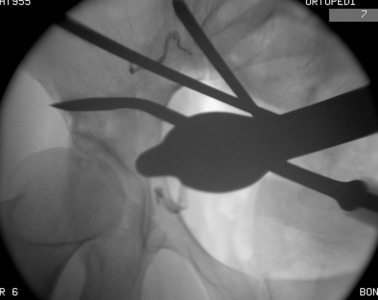

Prior to conducting the osteotomies, the greater sciatic notch, supraacetabular region, pubic rami, and quadrilateral surface were exposed, and the distances were measured as described by Shiramizu et al.15 The first osteotomy was performed on the supra-acetabular region and the iliac wing, from the pectineal line and aiming 1–2 cm distal to the medial of the anterior superior iliac spine (ASIS) (Fig. 4 ). The second osteotomy was performed on the posterior colon of the acetabulum, under fluoroscopic guidance with a 45° oblique view of the iliac. This osteotomy was from the pectineal line to the inferior ischium with an angle of 130° to the first osteotomy, leaving approximately 1 cm of bone posterior to the osteotomy line to preserve the posterior colon, as described in previously conducted anatomical studies (Fig. 5 ).15 The third osteotomy was performed on the pubic arm near to the acetabulum (Fig. 6  ;  Fig. 7 ). And the last osteotomy was performed on the distal ischium, parallel to the inferior acetabular rim (Fig. 8 ). Each stage of the operation was conducted under fluoroscopic control to ensure that the osteotome did not penetrate the joint. By twisting the osteotome under fluoroscopic guidance, it was ensured that the fragment was completely free. After completing the osteotomies, the acetabular fragment was medialized and rotated anterolaterally using a spike-tipped pusher. An anterolateral repositioning of approximately 20° was achieved under fluoroscopy. After the correction, the osteotomy was fixed with 2 or 3 3.5-mm screws (DePuy Synthes, Bettlach, Switzerland), which were inserted percutaneously from the iliac crest to the supraacetabular area, using 0.5- to 1-cm skin incisions.

The first osteotomy on the supra-acetabular region. From medial to lateral ...

Fig. 4.

The first osteotomy on the supra-acetabular region. From medial to lateral direction.